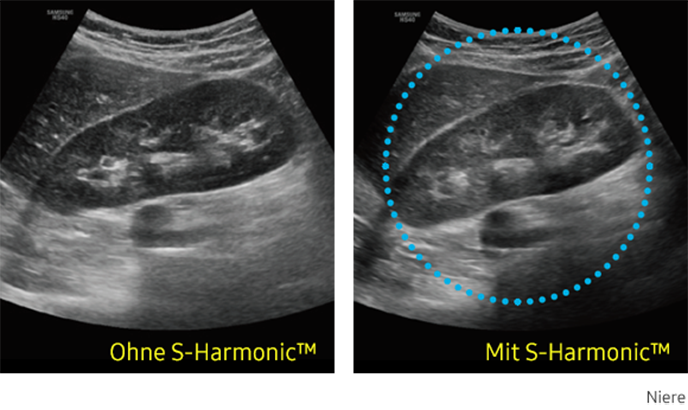

S-Harmonic

Diese neue Harmonic-Imaging-Technologie bietet Ihnen homogene Ultraschallbilder vom Nah- bis zum Fernfeld bei gleichzeitiger Rauschunterdrückung. Kombiniert mit den S-Vue™-Sonden und der S-Vision™ Imaging Engine erzeugt die HS40 Bilder in hoher Qualität.

Ultraschallbild Niere links ohne S-Harmonic und rechts mit S-Harmonic. Ultraschallbild Niere links ohne S-Harmonic und rechts mit S-Harmonic. Ultraschallbild Niere links ohne S-Harmonic und rechts mit S-Harmonic. Ultraschallbild Niere links ohne S-Harmonic und rechts mit S-Harmonic.